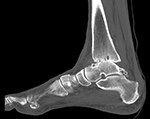

If you are a candidate for an ankle replacement, we will then obtain a CT (computed tomography) scan with multiple views creating a 3D assessment of your unique anatomy.

Your knee will be included in the CT scan to further improve alignment.

The CT scan allows us to create the patient-specific parameters used to plan and perform your surgical procedure with enhanced accuracy.